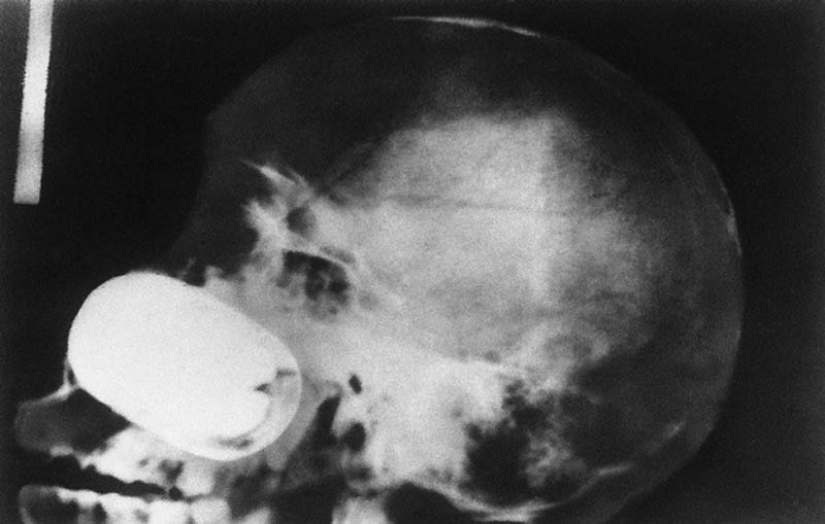

16. Grenade in the skull of the prisoner.